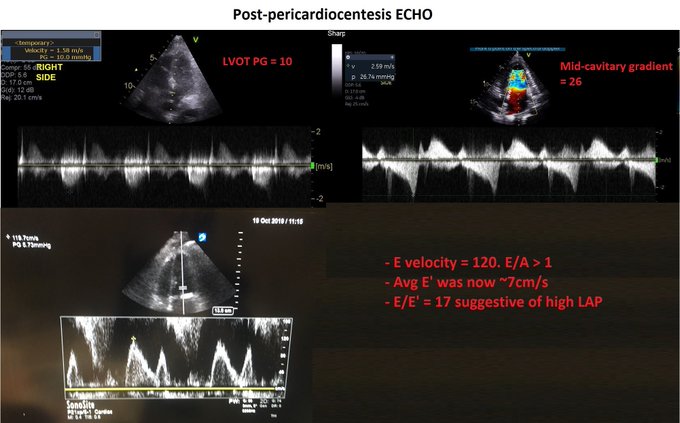

Managing the Congestive Heart Failure Patient – here, Philippe Rola introduces a physiologic and POCUS-based approach to the management of the admitted CHF patient, particularly with the management of effusions and venous congestion.